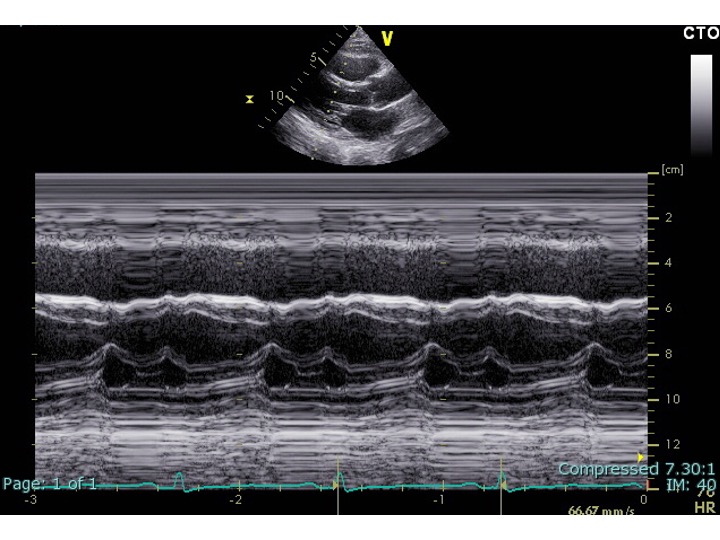

ransthoracic echocardiography was performed: Although the left ventricular ejection fraction was preserved, the inferior vena cava was dilated and showed no respiratory variation. There were pericardial adhesion and a septal bounce (Fig2-4). He was suspected of having constrictive pericarditis and was admitted for further evaluation.